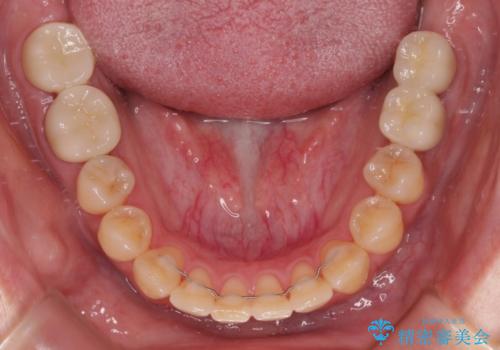

治療の期間と費用はかかりますが、初診時とは比べものにならないほど良好な状態にて治療を終えることができました。